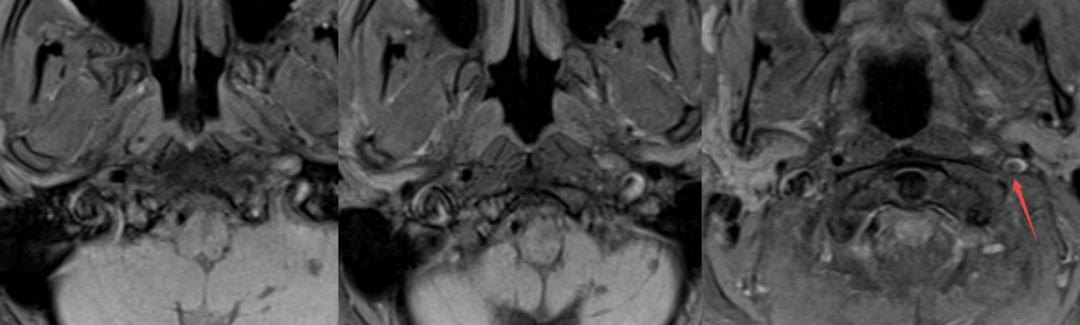

老年女性,急性起病,突发颈后部疼痛伴右侧肢体麻木无力,右侧肢体肌力2级。

答案:脊髓硬膜外血肿。补充病史既往长期服用华法林。患者临床以麻木,肢体无力卒中样起病。但是有颈部疼痛病史,病史跟影像提示脊髓硬膜外血肿。脊髓硬膜外血肿可能是自发的,也可能是继发于创伤、凝血功能障碍或麻醉操作。危险因素包括高龄、女性、创伤、血管畸形、抗凝治疗和高血压。提醒注意的是这样的患者有可能在绿色通道中被当做急性卒中患者被溶栓。